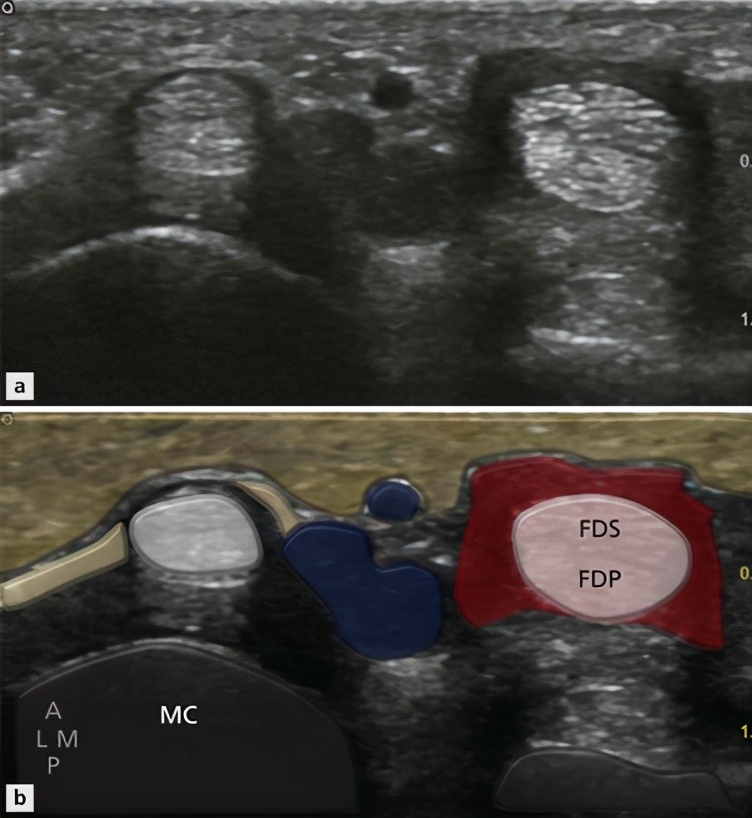

如果您想通过医学检查进一步的确诊自己存在着腱鞘炎或者是狭窄性腱鞘炎,可以去医院做一个检查叫做肌骨超声,通过这个超声我们可以判断患者手指周边的肌腱是否有明显的增粗,腱鞘是否有狭窄。

肌骨超声